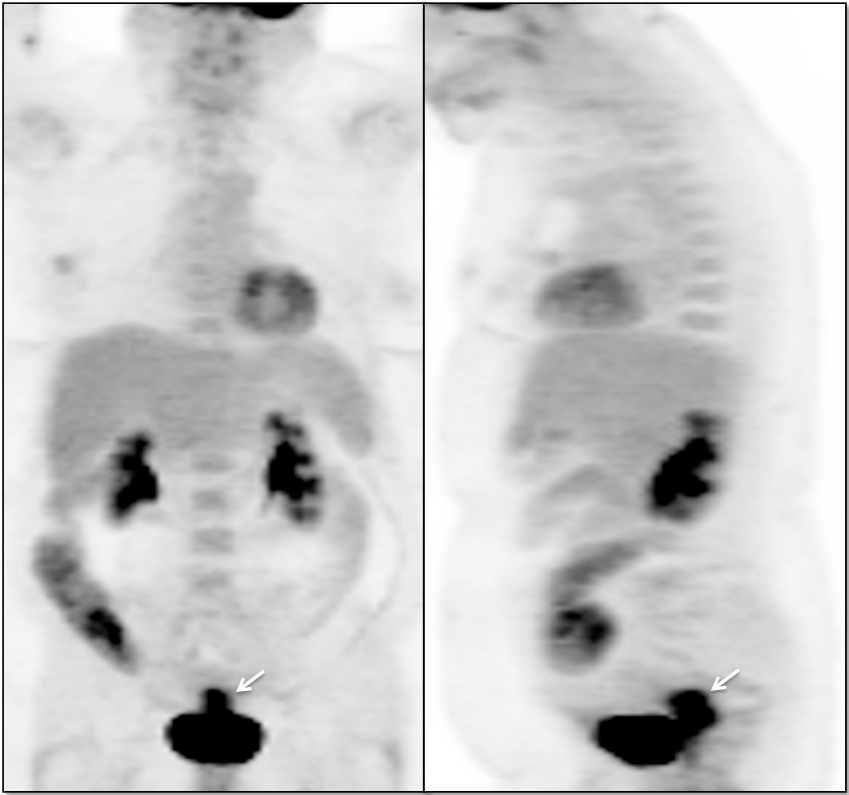

Recurrence, Restaging & Surveillance:

• PET/CT is utilized for patients with known or suspected recurrent disease (or at high risk for recurrence).

• Distinguishing recurrence from post-therapeutic inflammation.

• Lymphatic spread to pelvic and retroperitoneal lymph nodes.